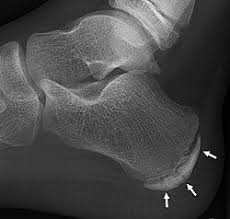

Pain occurs at posterior heel below Achilles attachment in children and adolescent athletes. Pain occurs during vigorous activity and ceases following activity. Two words in the name.

Sever's Disease